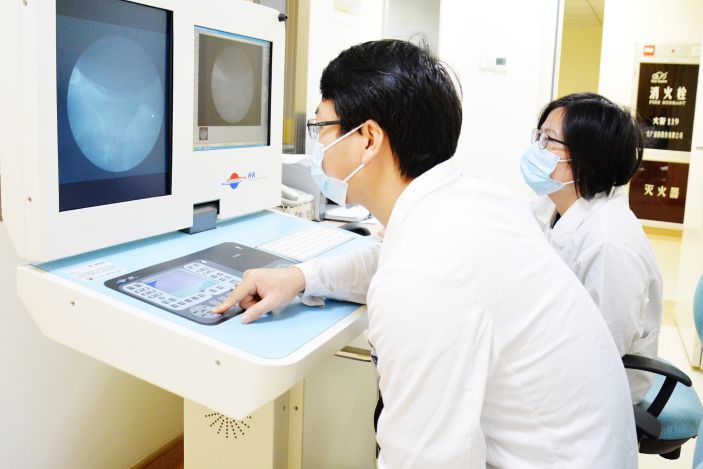

泌尿外科王海輝主治醫師介紹,體外碎石屬于物理排石,是在X光或B超引導下,通過體外碎石機發射沖擊波,作用于結石,經過多次釋放能量使結石粉碎,随尿液自行排出的技術。

體外碎石發射的沖擊波,其傳遞特點接近聲波。由于人體軟組織的聲阻抗與水接近,沖擊波傳入人體時幾乎沒有反射,能量損耗少,對軟組織幾乎沒有損害。而尿路結石的聲阻抗約爲水的5至10倍,聲阻抗的巨大差異,使沖擊波從人體組織到達結石後,對結石産生壓應力,使結石粉碎。